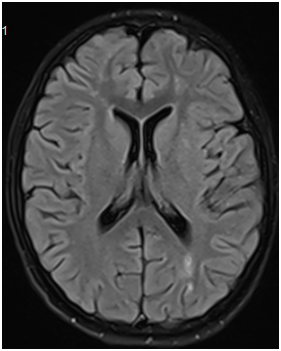

A 14-year-old female presented with subacute onset of random, unintentional movements involving the neck, trunk, limbs as well as facial muscles. The movements were sever enough to interfere with mobility. Otherwise she did not have any systemic complaints. Had no history of a recent infectious illness and did not use any medication. Her past and family history was unremarkable. On examination, she was alert, fully oriented with intact cognitive functions. The movements were noted as involuntary, rapid and purposeless generalized movements. She could not control it and had difficulty stabilizing her head. Auscultation revealed pansystolic murmur over the apex. She had no skin lesion, joint tenderness or swelling. Blood investigations showed normochromic normocytic anemia with thrombocytopenia (Hb: 8g/dl, MCV: 80 fl, WBCs: 4.5×10⁹ Platelets: 84×10⁹). Had normal renal and liver functions. Coombs test was positive, ANA and anti-dsDNA Abs were positive. Furthermore her cardiolipin IgG was positive (36.9 U/ml) and urine analysis shows hematuria (20-30/HPF) and proteinuria (100 mg/dl). Brain MRI demonstrated multiple bilateral old and recent ischemic lesions (Figure 1). Echocardiography show mildly thickened mitral valve with prolapsed of anterior segments of mitral leaflet & moderate mitral regurgitation.

Figure 1 (A & C) FLAIR and (B & D) Diffusion-weighted images of the brain showing multiple small infarctions at different ages (old and recent) involving the deep white matter of both cerebral hemispheres. The acute infarcts show diffusion restriction on B & D, while old infarctions show low signal on FLAIR images with surrounding gliosis.